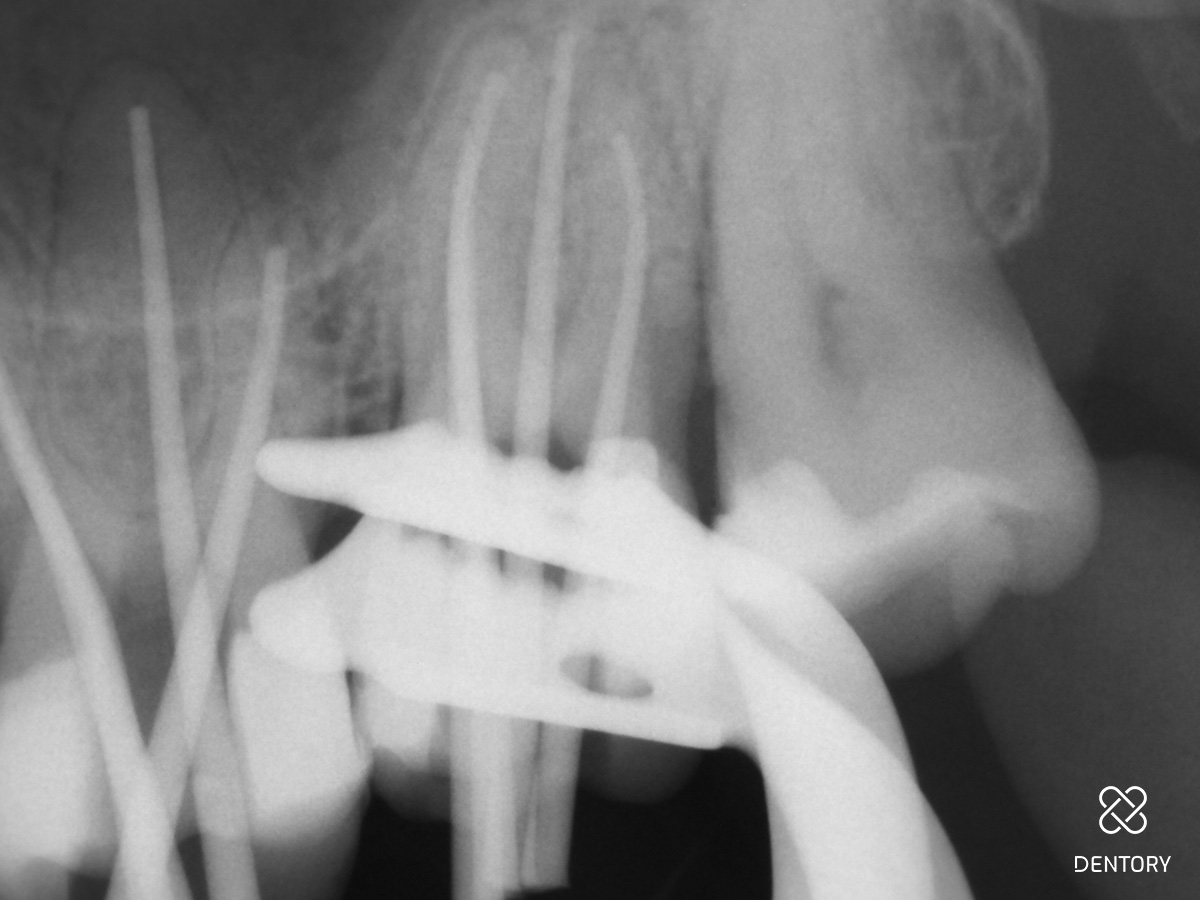

Abbildung 8

Händische Guttapercha-Entfernung: Entfernung der Guttapercha, die über die Konstriktion hinaus geht mit einer Hedström-Feile ISO 25.